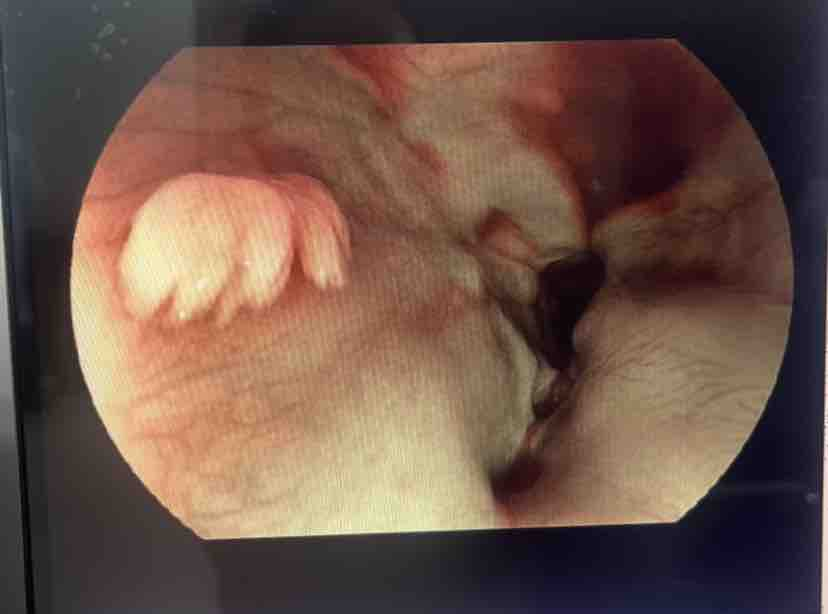

近日,古蔺县中医医院肺病·脾胃病·内分泌科开展1例内镜下息肉切除术。患者张某(化名),女,48岁,因“反复剑突下疼痛1年余。”来医院就诊。经胃镜检查发现,其胃体内存在多发性息肉,其中可见3枚大小约3-6mm的息肉样隆起,胃体前壁见两条线性虫体蠕动,经与家属充分沟通后,为其施行了内镜下胃息肉切除术。手术过程中,通过内镜将专用器械送至病变部位,精准地切除了所有可见息肉,并进行胃窦前壁、胃体交界处病理活检。术后患者恢复良好,无明显不适感。术后病理证实为:炎性息肉、考虑慢性非萎缩性胃炎。

患者胃镜术前术后对比图片